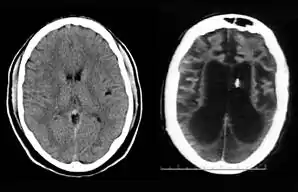

Left: CT scan of normal brain; Right: Schiavo's 2002 CT scan provided by Ronald Cranford, showing loss of brain tissue. The black area is liquid, indicating hydrocephalus ex vacuo.[33] The small white piece in the right image is the thalamic stimulator implanted in her brain.

On August 10, 2001, on remand from the Florida Second District Court of Appeal, Judge Greer heard a motion from the Schindlers claiming that new medical treatment could restore sufficient cognitive ability such that Terri Schiavo herself would be able to decide to continue life-prolonging measures. The court also heard motions from the Schindlers to remove the guardian (Michael Schiavo) and to require Judge Greer to recuse himself. Judge Greer denied the motions and the Schindlers appealed to the Second District Court of Appeals. On October 17, 2001, the Court of Appeal affirmed the denials of the motions to remove and recuse. The Court of Appeals acknowledged that their opinion misled the trial court, and they remanded the question of Terri Schiavo's wishes back to the trial court and required an evidentiary hearing to be held. The court specified that five board certified neurologists were to testify. The Schindlers were allowed to choose two doctors to present findings at an evidentiary hearing while Schiavo could introduce two rebuttal experts. Finally, the trial court itself would appoint a new independent physician to examine and evaluate Terri Schiavo's condition. (These decisions, all published in a single order by the Florida Second District Court of Appeal,[34] came to be known by the court as Schiavo III in its later rulings.) In October 2002, on remand by the Second District Court of Appeal, an evidentiary hearing was held in Judge Greer's court to determine whether new therapy treatments could help Terri Schiavo restore any cognitive function. In preparation for the trial, a new computed axial tomography scan (CAT scan) was performed, which showed severe cerebral atrophy. An EEG showed no measurable brain activity. The five physicians chosen were William Maxfield, a radiologist, and four neurologists: William Hammesfahr, Ronald Cranford, Melvin Greer and Peter Bambakidis.[35]

The five doctors examined Terri Schiavo's medical records, brain scans, the videos, and Terri herself. Cranford, Greer, and Bambakidis testified that Terri Schiavo was in a persistent vegetative state (PVS). Drs. Maxfield and Hammesfahr testified that she was in a minimally conscious state. As part of the court-ordered medical exam, six hours of video of Terri Schiavo were taped and filed at the Pinellas County courthouse. The tape included Terri Schiavo with her mother and neurologist William Hammesfahr. The entire tape was viewed by Judge Greer, who wrote, Terri "clearly does not consistently respond to her mother". From that six hours of video, the Schindlers and their supporters produced six video clips intended to support their case, totaling less than six minutes, and released those clips to public websites.[1] Judge Greer ruled that Terri Schiavo was in a PVS, and was beyond hope of significant improvement. The trial court order was particularly critical of Hammesfahr's testimony, which claimed positive results in similar cases by use of vasodilation therapy, the success of which is unsupported in the medical literature.[36] This ruling was later affirmed by Florida's Second District Court of Appeal, which stated that "this court has closely examined all of the evidence in the record", and "we have ... carefully observed the video tapes in their entirety." The court concluded that "if we were called upon to review the guardianship court's decision de novo, we would still affirm it." This decision by the Second District Court of Appeals[37] came to be known as Schiavo IV in later rulings.